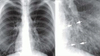

31

Q es y como sabes

bronquitis crónica x la imagen en tranvía q habla de bronquiectasia